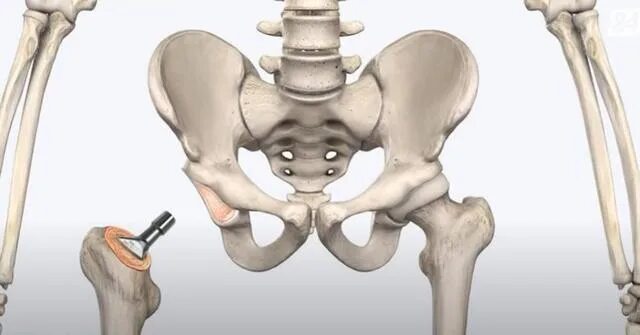

Протезы тазобедренных суставов по квоте